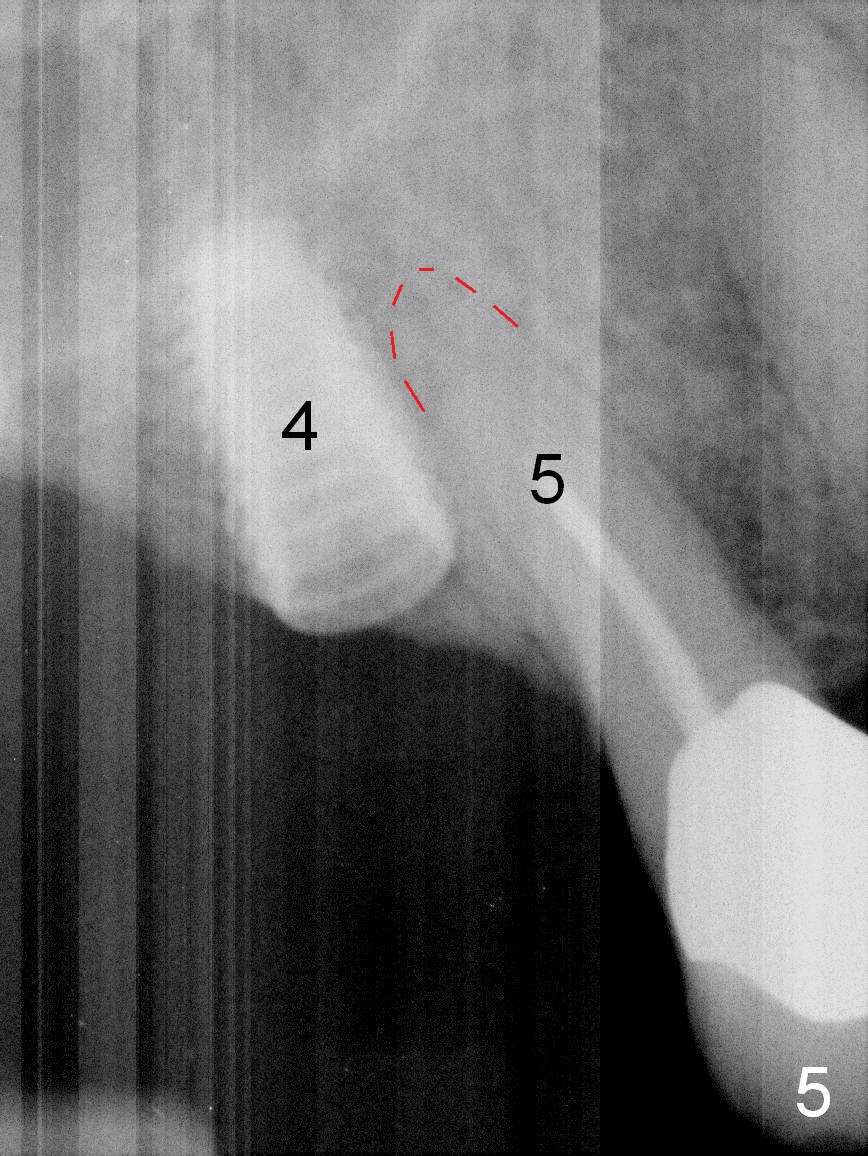

After use of 2.8 mm round bur at #4 for sinus lift, a 4x8.5 mm regular drill is used with resultant sinus membrane perforation at the sinus floor. The latter is repaired with insertion of Osteogen plug prior to place 4.5x8.5 mm implant (Fig.5,6). The similar mistake occurs at #3: after using 2.4/3.7 mm bone expander for 10 mm, a 4x10 mm is used, which also results in sinus perforation, probably sideway, buccally. Trimmed Osteogen plug is placed before a 4.5x10 mm implant is placed with primary stability (Fig.6). The reason for use of the regular drills is to avoid ridge fracture due to under prep.